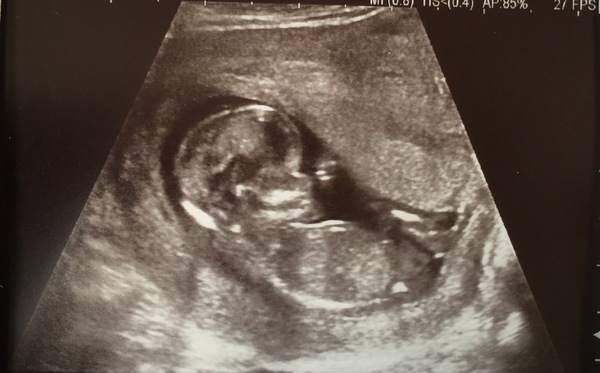

12 week scan was yesterday! I was absolutely terrified as it was at my 12 week scan last time that I discovered I'd had a missed miscarriage. I nearly broke down in tears in the waiting room, I was so nervous. Well...

Baby is just fine ❤️ Measured at 12+5 and wiggling away on the screen. Couldn't be more ecstatic ❤️

@CobaltRose omg, more lovely news on the thread today. How cute does your baby look, that's an awesome scan pic.

@CobaltRose excellent news, congratulations! And such a perfect scan picture!